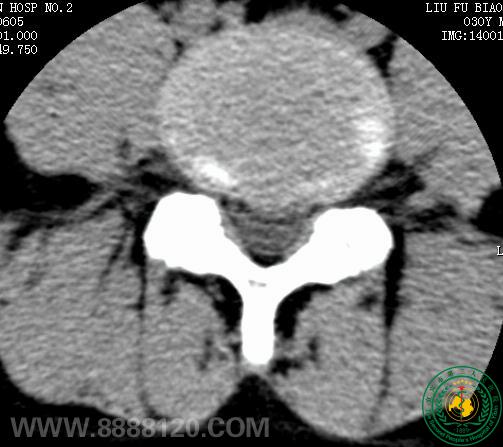

患者为30岁青年男性,经我院CT扫描诊断为腰4/5正中后型椎间盘突出症。经我科李登科、林川两位主治医师术前严格筛查及讨论,认为该患者适合进行臭氧髓核消融,无该手术禁忌症,遂于69日晨830分在经严格消毒后的介入手术室完成了该例手术。术中及术后患者未诉不适。术后于我院CT室复查,见腰4/5椎间盘髓核区臭氧存留。

椎间盘穿刺(2                                                                         术后CT